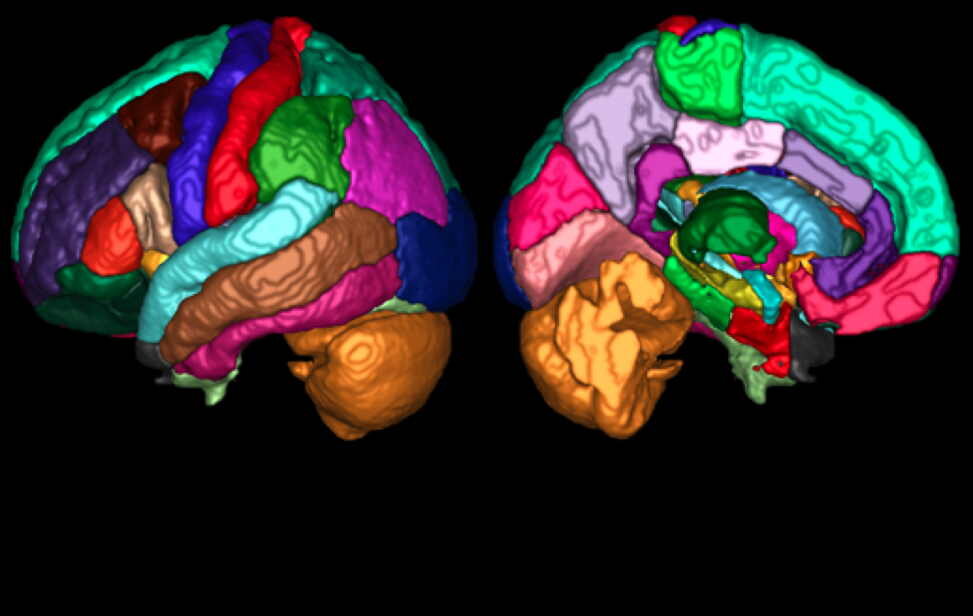

Атласы мозга широко используются при визуализации мозга, чтобы связать структурную или функциональную метку с положением в системе координат, часто определяемым в пространстве опорного сигнала мозга, таком как MNI 305. Атласы, как правило, состоят из серии изображений или одного разделенного изображения, типичного или усредненного мозга. Они используют либо жесткие метки (ноль, одна или несколько меток для данной позиции), либо вероятностную информацию, указывающую на вероятность наличия метки в определенном месте. Атласы существуют как для 3D, так и для поверхностной геометрии и могут представлять различные типы информации (например, цитоархитектоническая или анатомическая макроскопическая сулькогиральная информация, функциональная информация и т.д.). Хотя большинство исследователей в области нейровизуализации обычно используют один или несколько атласов мозга в своем анализе, формат данных этих атласов различается. Это означает, что для извлечения информации будет необходим специализированный процесс, а сравнение результатов анализа будет затруднено. Например, Harvard-Oxford (HO), Automatic Anatomical Labelling (AAL), Freesurfer и JuBrain относятся к наиболее часто используемым атласам и не представляют метаданные или другую информацию в едином формате. Также растет число других функциональных разделов и атласов функциональных сетей.

Хотя атласы мозга широко распространены и их число растет, на текущий момент не существует стандартного способа описания содержащейся в них информации, даже для очень похожих типов атласов, таких как HO и AAL. Это неэффективно для разработчиков и приводит к возникновению ошибок, затрудняя комбинирование атласов и осложняя проведение экспериментов и сравнений данных. В более широком смысле, отсутствие четкого описания и формата делает неясной концепцию атласа (по сравнению с шаблоном или системой координат).